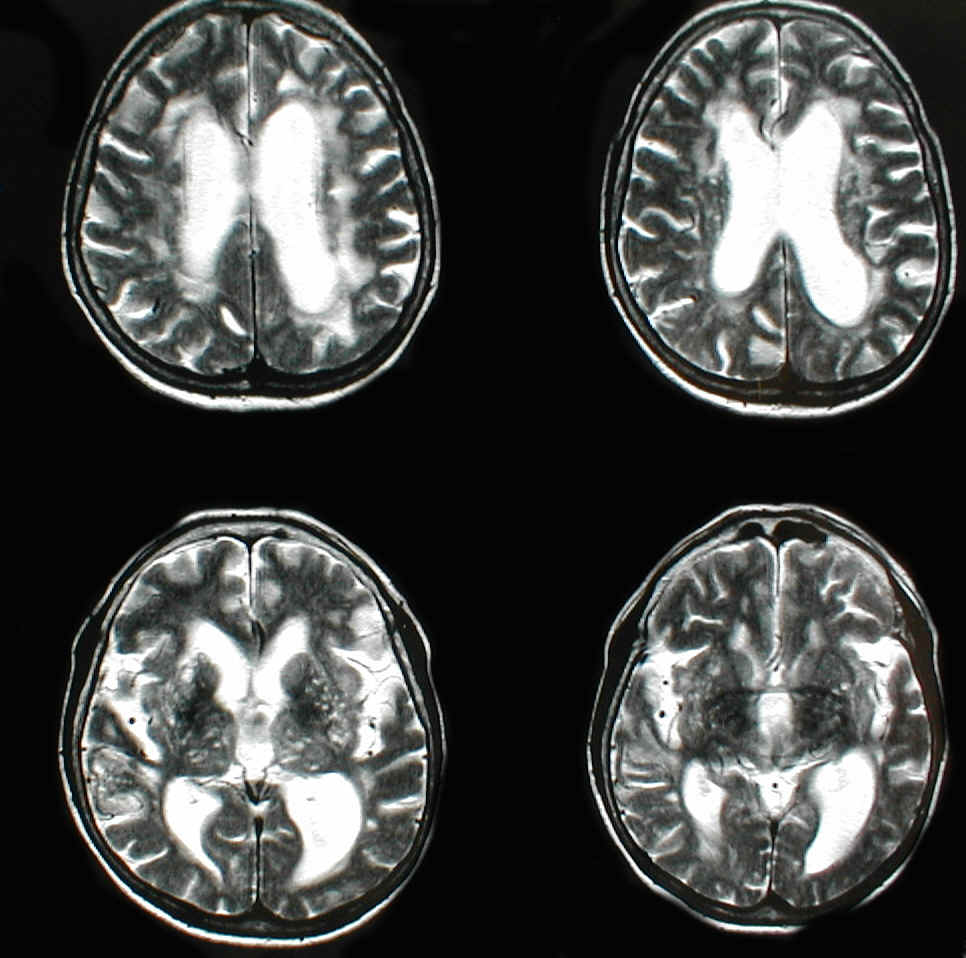

Die bildgebenden Verfahren wie Kernspintomographie (MRI), Computertomographie (CT) und bei Säuglingen und Kleinkindern auch Ultraschalluntersuchungen stellen heute nach Anamnese und klinischem Befund die Haupt-Säule der Hydrocephalusdiagnostik dar. Klassische Befunde sind bei der Beschreibung der einzelnen Unterformen des Hydrocephalus dargestellt.

Allgemein gesagt, sollte aber typischerweise ein Missverhältnis der Weite der inneren (Ventrikel) und äußeren Liquorräume bestehen. Die inneren Liquorräume sind weit, die äußeren eng. Dies wäre typisch. Je nach Unterform des Hydrocephalus, kann es aber sein, dass lediglich die vertexnahen (also die direkt unter dem Schädeldach liegenden) äußeren Liquorräume eng sind.

Ideal ist es eine Kernspintomographie zu haben, da hier einerseits teilweise die Ursache des Hydrocephalus unmittelbar zu sehen ist und auch Therapiealternativen damit besser abgewogen werden können.

Der größte Vorteil der MRI ist aber, dass man gerade beim älteren Menschen, wo neben dem Hydrocephalus ggf. noch andere Erkrankungen bestehen können (Hirndurchblutungsstörungen, Hirnabbau-Erkrankungen anderer Art). Teilweise können diese mit dem MRI bereits visualisiert werden und damit auch besser abgeschätzt werden, ob eine Therapie für den Patienten sinnvoll erscheint oder aber der Hydrocephalus eher einen "Nebenkriegsschauplatz" darstellt.

Das oben dargestellt MRI ist ein gutes Beispiel, welche Hilfe ein MRI bei der Beurteilung des weiteren Vorgehens und bei der Beratung des Patienten sein kann: Zwar sieht man schon eine Diskrepanz der Weite der inneren und äußeren Liquorräume, sodass grundsätzlich die Verdachtsdiagnoste Hydrocephalus im Raume steht. Man sieht aber auch Veränderungen in der Hirnsubstanz selbst, die auf eine zusätzliche Hirnerkrankung, nämlich eine schwere Hirndurchblutungsstörung in diesem Falle hindeuten. Mit dieser Klarheit ist dies mit einem CT kaum zu erkennen. Als unabdingbare Forderung zur Diagnose eines Hydrocephalus gilt, dass der Evans Index (bestimmtes Messverfahren zur Ermittlung der Ventrikelweite > 0,3 sein muss.